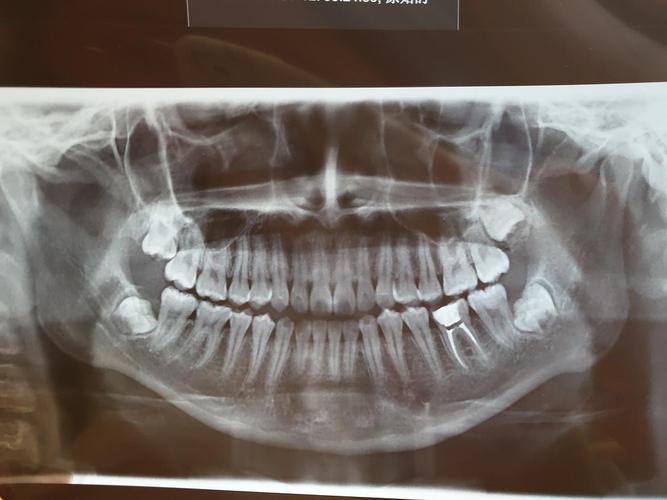

根管治疗小牙片

根管治疗小牙片,根管治疗的根管图片

根管治疗的根管图片

根管治疗图片